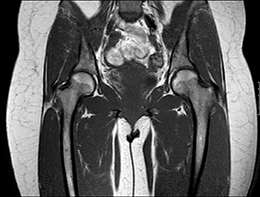

Die MRT ist hinsichtlich der Darstellbarkeit von verschiedenen Organen, Gefäßen, Bändern und Gelenken vielen anderen heute in der Radiologie zur Verfügung stehenden bildgebenden Verfahren überlegen. Insbesondere Entzündungsherde und vitale Tumoren können mit der MRT häufig besser erkannt werden als mit anderen Verfahren.

Bei 3,0 Tesla-MRT-Geräten (stärkeres Magnetfeld) können mitunter Wärmegefühle auftreten, insbesondere bei Untersuchungen der Bauch- und Beckenregion. Ausserdem ist das Risiko einer Interaktion mit Implantaten (wie z.B. Zahnplomben) höher. Bei modernen 1,5 Tesla-Geräten sind stärkeres Wärmegefühl oder Schwitzen während der Untersuchung sehr selten. Deshalb bieten aus unserer Sicht die im IRNB eingesetzten 1,5 Tesla-MRT-Systeme einen sinnvollen Kompromiss aus sehr guter Abbildungsqualität und geringer Patient_innenbelastung.